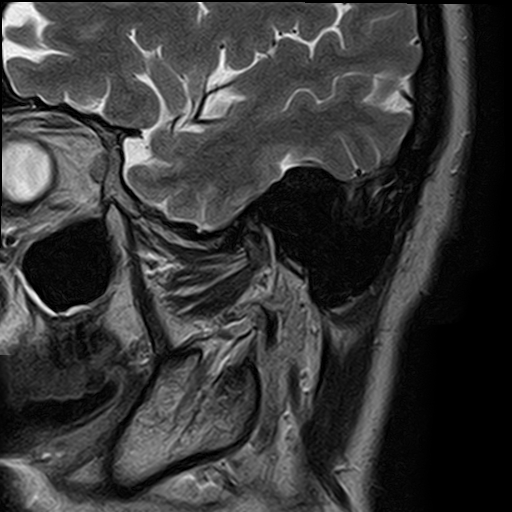

Височно-нижнечелюстной сустав является парным комбинированным суставом и имеет сложное строение. В него входят суставные ямки височной кости, суставные головки нижней челюсти и расположенные между ними хрящевые пластинки – мениски, выполняющие роль амортизаторов.

Чаще всего дисфункция височно-нижнечелюстного сустава обусловлена внутренним повреждением, смещением мениска и суставной головки нижней челюсти. Для определения степени смещения внутрисуставных структур выполняется функциональная проба с проведением МРТ в двух положениях:

Магнитно-резонансная томография является наиболее точным и эффективным методом диагностики поражения височно-нижнечелюстных суставов, так как позволяет получить детальную информацию о состоянии не только костей, но и связочного аппарата, хрящей, менисков, жевательных мышц, окружающих мягких тканей.

При проведении магнитно-резонансной томографии на изображениях визуализируются: височная кость, головка мыщелкового отростка нижней челюсти, суставная щель. Помимо костных структур МРТ позволяет оценить состояние мягких тканей – внутрисуставного диска и связочного аппарата височно-нижнечелюстного сустава, жевательных мышц.